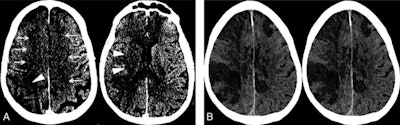

Image A: Noncontrast CT on the day of admission demonstrates subtle findings of acute ischemia in the right middle cerebral artery (arrowheads) and bilateral anterior cerebral artery (arrows) territories, including hypoattenuation and loss of gray-white differentiation. Image B: Repeat noncontrast CT on hospital day two demonstrates progression of acute infarcts in the right middle cerebral artery and bilateral anterior cerebral artery territories, including worsening edema and mass effect. Image courtesy of AJNR.Data about COVID-19 gathered around the world suggests 5% to 6% of patients with severe cases may suffer a cerebrovascular injury.

The current case study from Allegheny Health Network Stroke Center in Pittsburgh is of a 64-year-old man who presented to the emergency department after waking up at home with symptoms of left-sided paralysis and shortness of breath. He had tested positive for COVID-19 16 days prior and was recovering well before his sudden onset of ischemic stroke. The patient passed away from complications of COVID-19 three days after admission to the hospital.